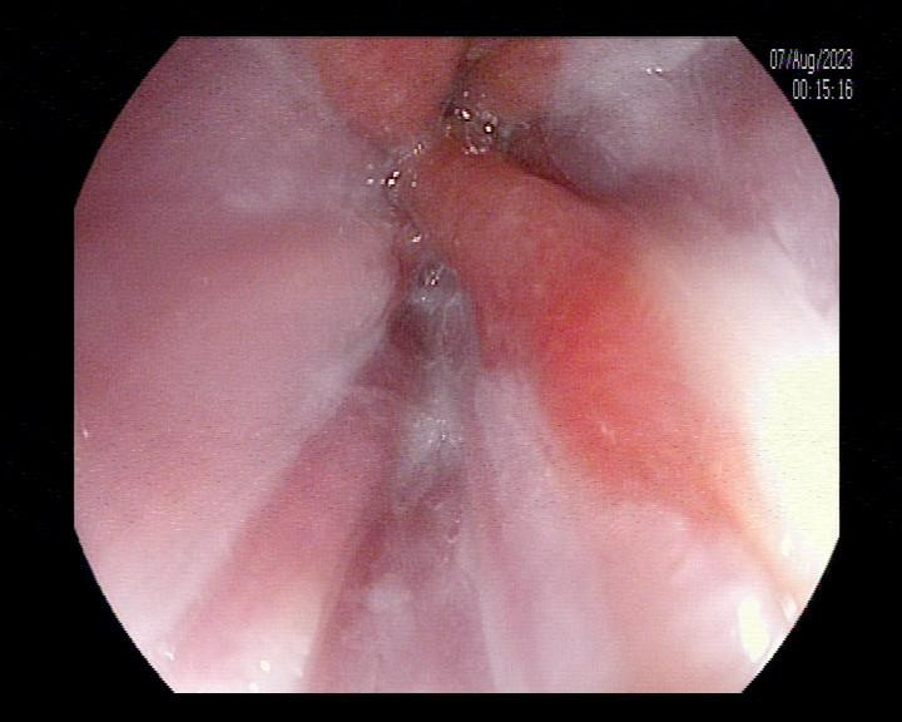

Nội soi đường tiêu hóa trên và làm sinh thiết tế bào giúp các Bác sĩ xác định được người bệnh có mắc Barrett thực quản hay không và mức độ tiến triển của bệnh thế nào để có những phương pháp điều trị hợp lý và chính xác. Phần lớn barret thực quản không có loạn sản, người bệnh nên nội soi định kì 6 - 12 tháng để theo dõi sự tiến triển của các tế bào trong thực quản.